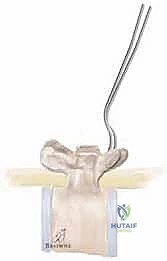

This is the most perilous phase of the procedure. The ligamentum flavum is meticulously excised at the midline using Kerrison rongeurs to expose the epidural space. Doubled 16-gauge or 18-gauge stainless steel wires, pre-bent into a smooth, semi-circular loop, are carefully passed under each lamina.

The technique requires a delicate "flossing" motion. The tip of the wire must be kept in direct contact with the undersurface of the lamina at all times to avoid plunging into the spinal cord.

Once the loop emerges from the cephalad edge of the lamina, it is grasped with a nerve hook and pulled through. The wires are then sharply bent over the posterior elements to prevent them from slipping back into the canal and compressing the cord.